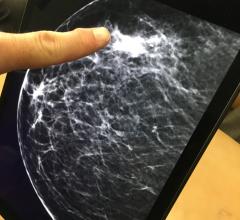

Mammography is a breast imaging technique that uses X-rays to diagnose and locate tumors of the breasts.

Despite decades of progress in breast imaging, one challenge continues to test even the most skilled radiologists ...